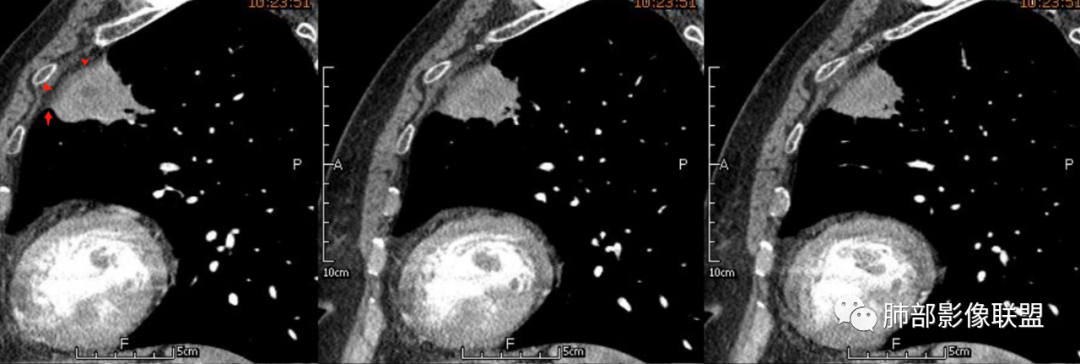

宽基底,附近胸膜增厚,边缘平直

支气管通畅

血管走形自然

坏死灶边界清附近卫星灶

意见:支持炎性。治疗后复查以排除恶性病变隐藏其中

1、坏死区环形强化,指向慢性脓肿。

2、坏死区有血管,基本排除结核。

3、这个卫星灶,更进一步定了大方向,炎性。

※综上所述,看到这四幅图,基本能够准确诊断炎性※